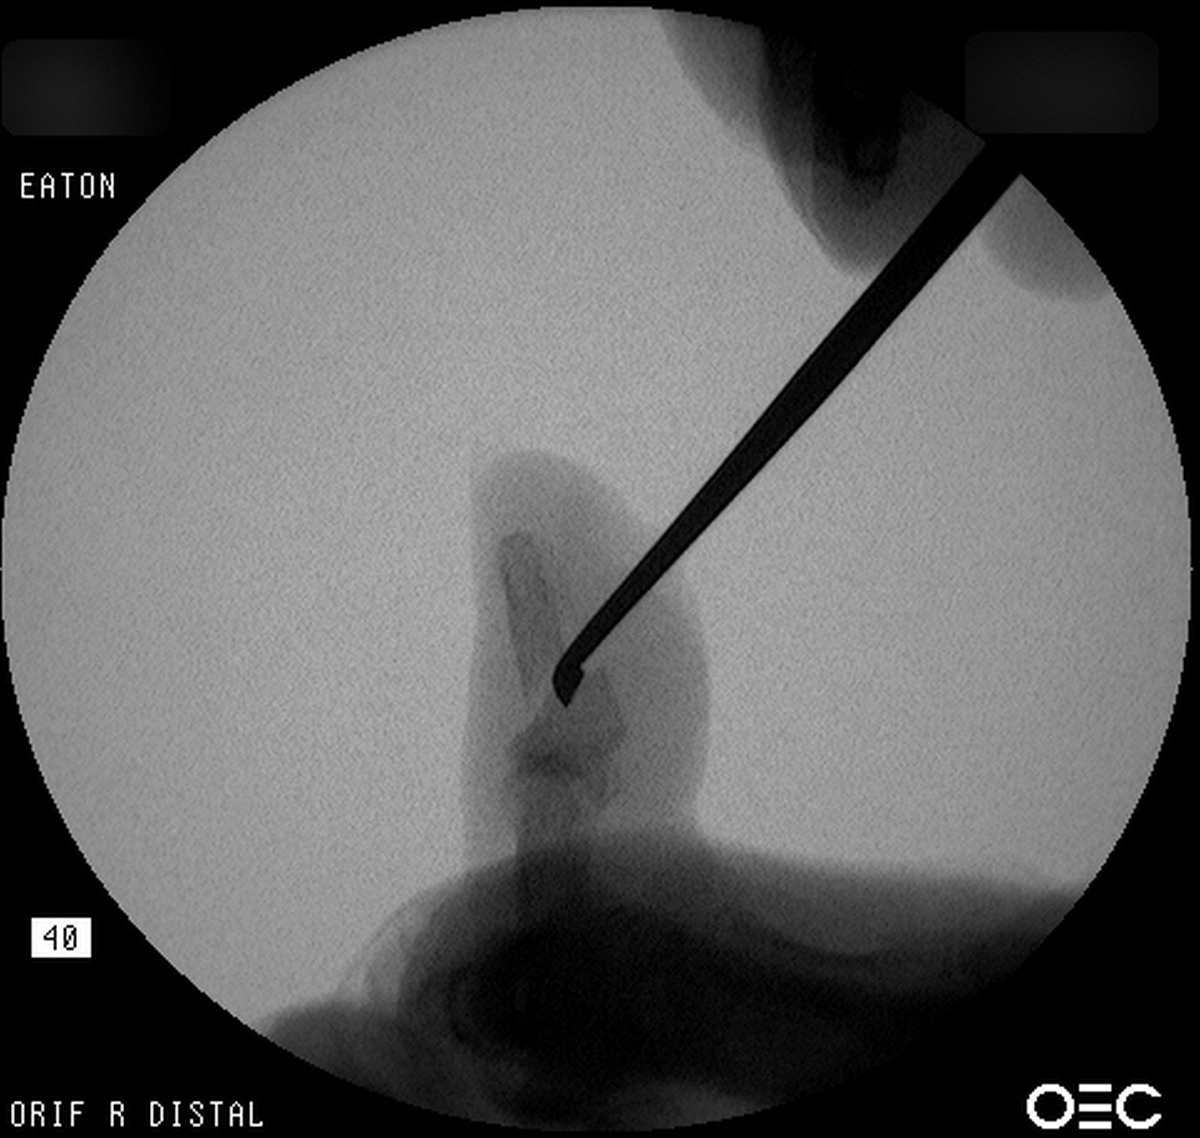

| Freer elevator

introduced percutaneously as a reduction aid. |

| Percutaneous

fracture stabilization with three pins via the

dorsal radial tubercle, radial styloid and FCR

portals. |